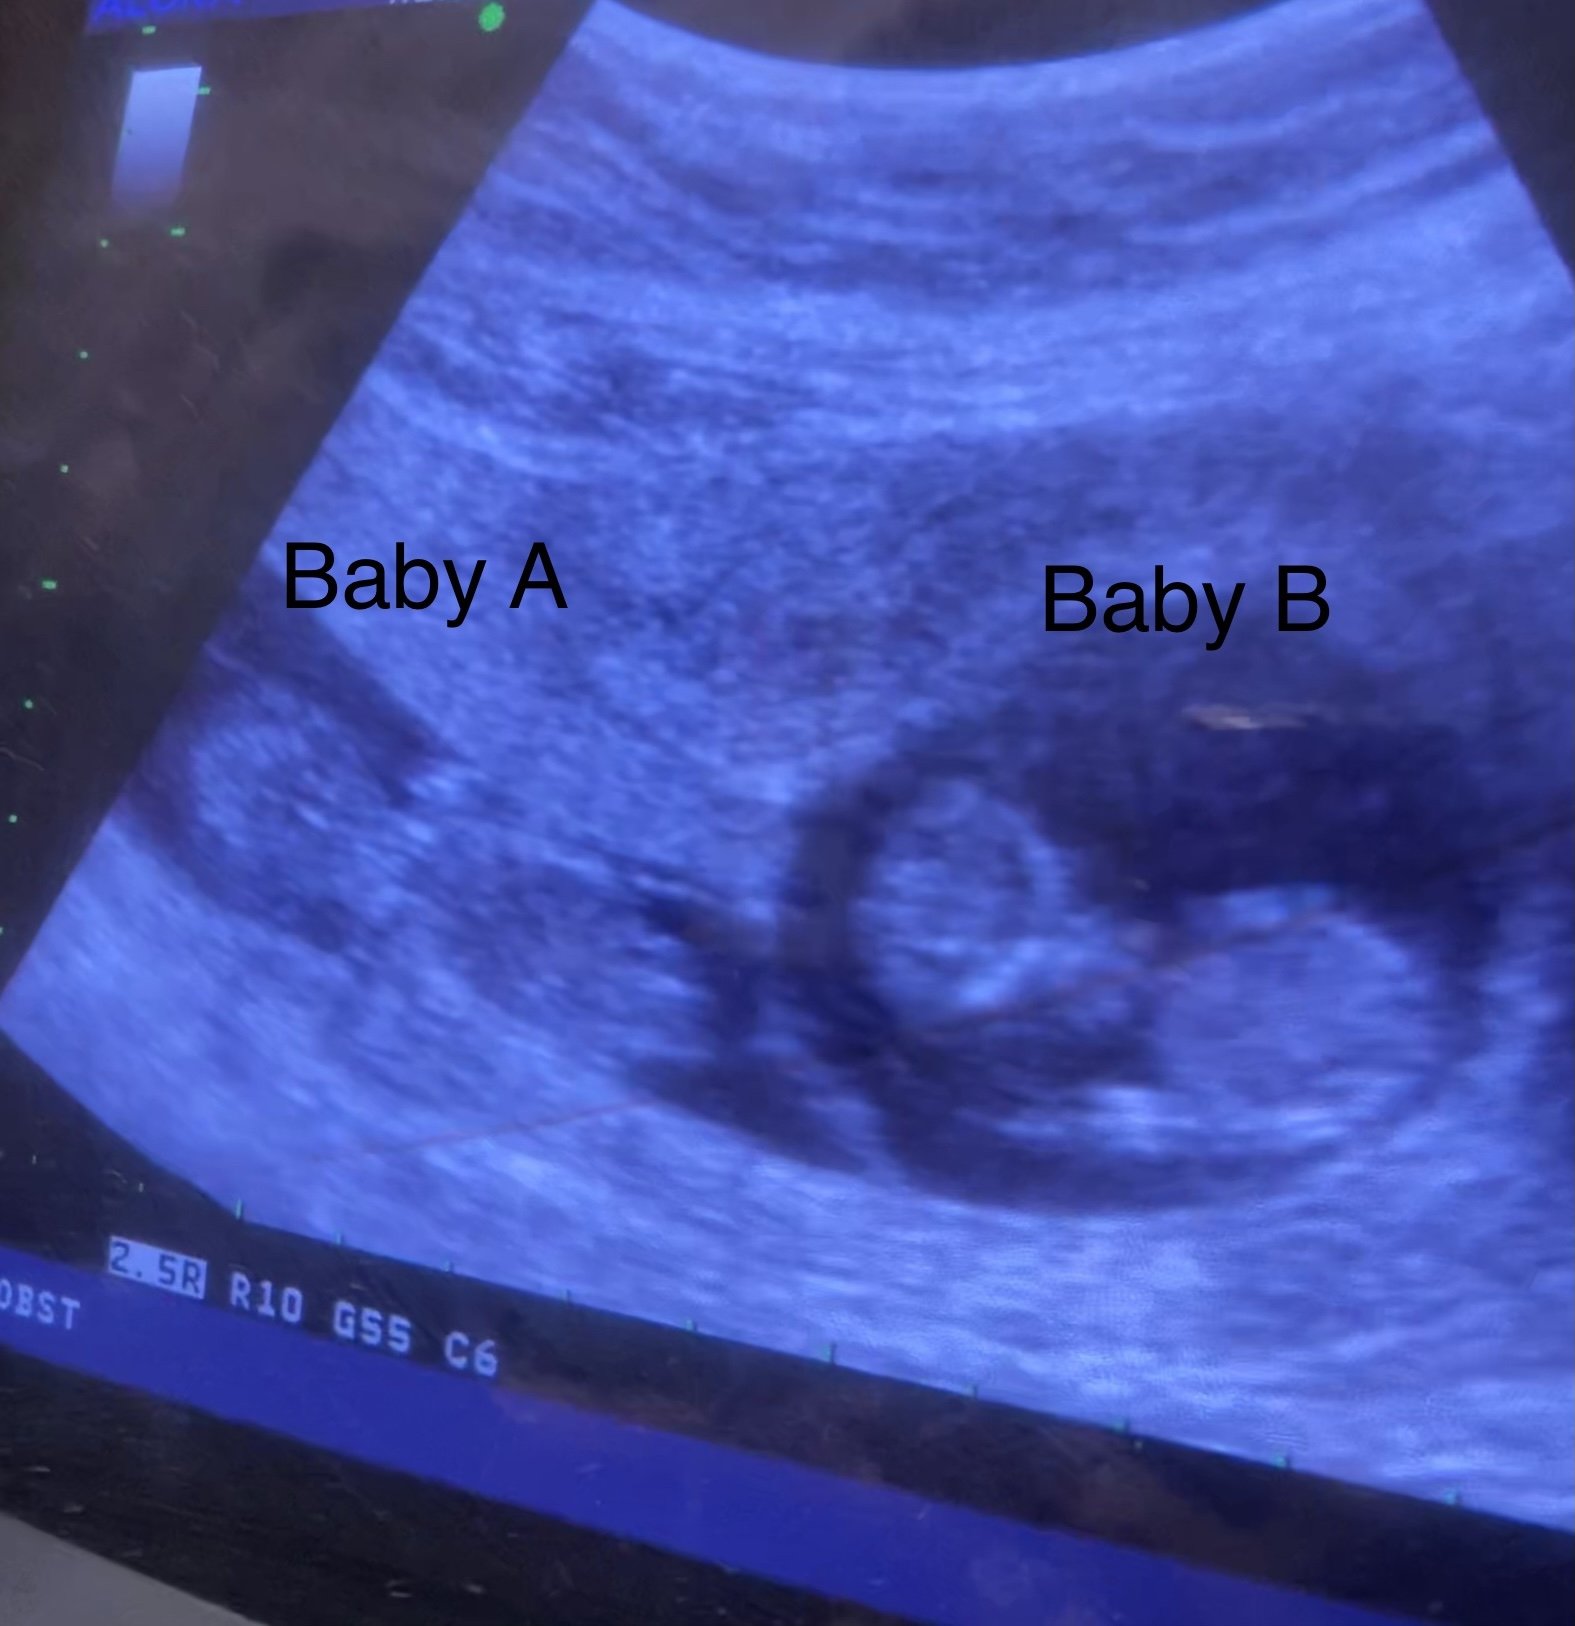

Well I am a unicorn as my pregnant buddy says with having no symptoms other then the positive on the test and no period. Had our ultrasound today and got to see the baby measuring right on track.